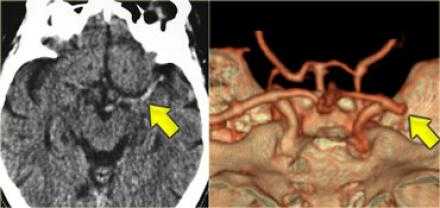

Симптом плотной СМА.

Данный симптом проявляется в следствии тромбирования или эмболизации СМА. У ниже представленного пациента симптом плотной СМА. На КТ ангиография визуализируется окклюзия СМА.

В данном случае признаки инфаркта едва уловимые. Гиподенсная зона в островковой области справа. В данном случае эти изменения соответствуют инфаркту, но у пожилых пациентов с лейкоэнцефалопатией тяжело отдифференцировать эти две разные патологии.

Вышележащие изображения — КТ-ангиография. После выполнения КТА — диагноз инфаркта в области СМА, как на ладоне.